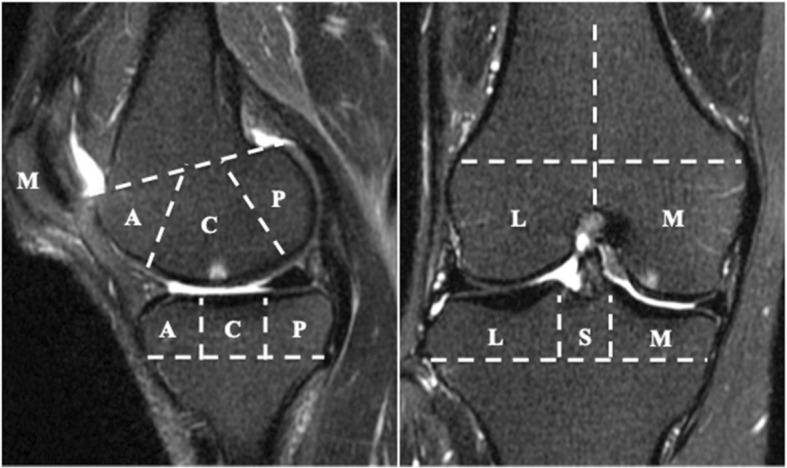

All participants underwent MRI of the right knee using a rapid extremity coil and mobile magnetic resonance unit (1.5 T; ECHELON RX, Hitachi, Tokyo, Japan) within 1 week after other examinations. The participants were positioned supine with their knees in full extension. Sequences included sagittal and coronal T2-weighted fat saturation fast spin echo (repetition time 5000 ms; echo time 80 ms; field of view 16 cm; 288 × 288 matrix; slice thickness of 3 mm with a between-slices gap of 1.0 mm). BMLs were defined as the area of an irregular hyperintense signal in the subchondral bone. The area was measured semi-quantitatively using the Whole-Organ MRI Scoring (WORMS) method [28] in 15 subregions. Specifically, the medial and lateral compartments of the tibia and femur were divided into 3 subregions (anterior, central, and posterior), and the tibia had 1 additional subregion, representing the area beneath the tibial spine. The patella was divided into medial and lateral subregions (Fig. 1). BMLs were each scored as integers from 0 to 3, where 0 = normal; 1 = mild, < 25% of the region; 2 = moderate, 25–50% of the region; and 3 = severe, > 50% of the region (Fig. 2). The total BML score, which reflected severity, was calculated as the sum of the 15 subregional scores. BML was considered present if the total BML score was greater than zero. Two independent observers (DC and ES) scored MR images in a blinded fashion with no access to the participants’ clinical information. The inter-rater reliability, expressed as interclass correlation coefficients [ICC] (2.1) of scoring BML on 100 randomly selected MR images, was 0.873 (95% confidence interval [CI] 0.815–0.914, p < 0.001).

Fig. 1.

Regional subdivision of the articular surfaces for the assessment of bone marrow lesions (BMLs). BMLs were assessed by the Whole-Organ MRI Scoring (WORMS) method. The patella, femur, and tibia were divided into medial (M) and lateral (L) regions. Region S represents the portion of the tibia beneath the tibial spines. The femoral and tibial surfaces were further subdivided into anterior (A), central (C), and posterior (P) regions